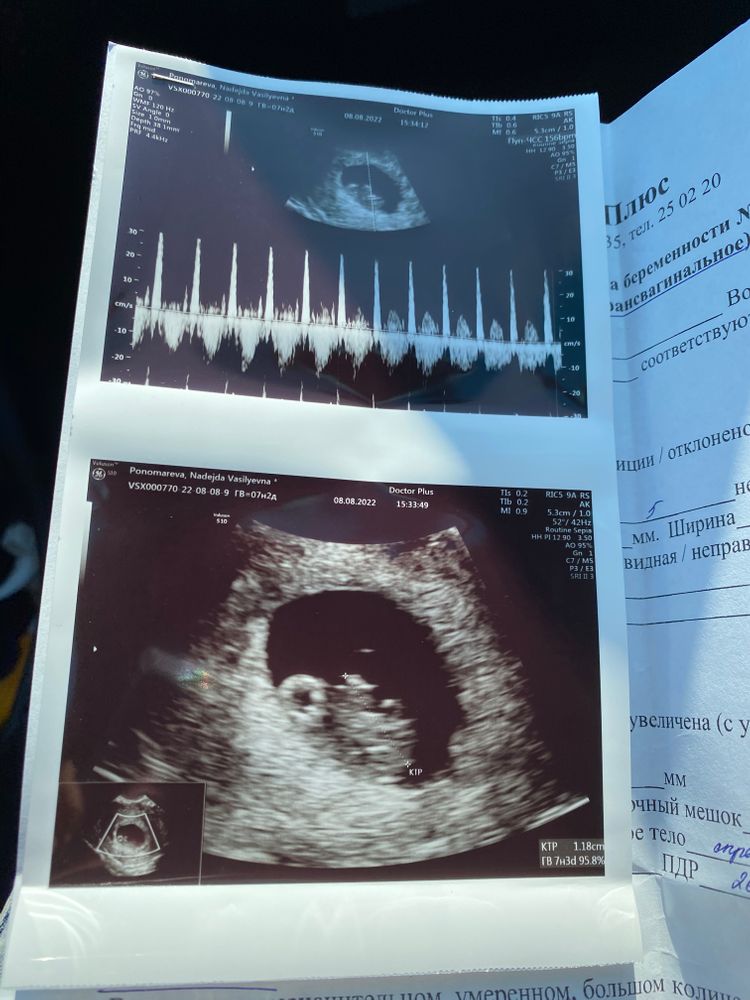

6.07.2022 состоялся криоперенос 2х пятидневок 4АА и 3ВВ в клинике Ава Петер🤞🏽🤞🏽🤞🏽